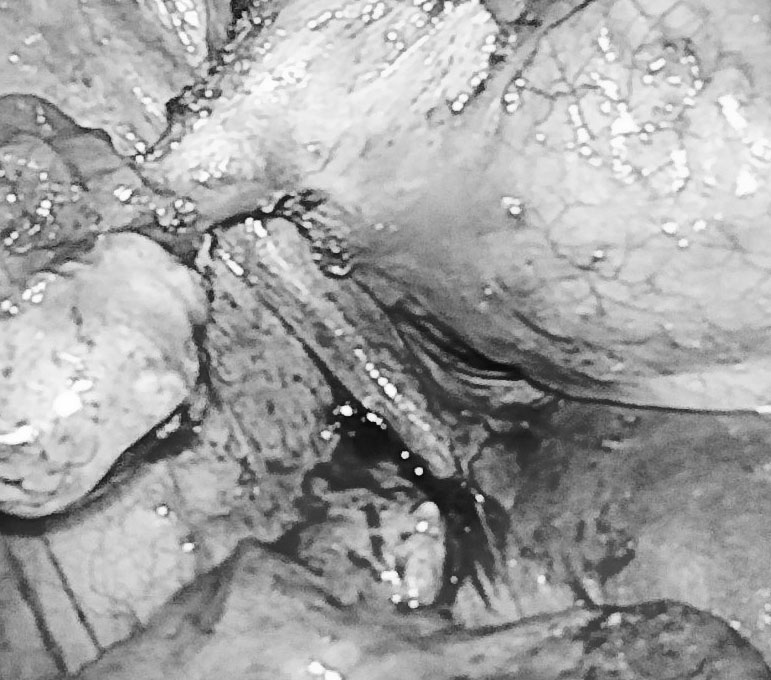

Qua thăm khám và thực hiện các cận lâm sàng cần thiết, kết quả nội soi bàng quang phát hiện vùng đỉnh bên trái bàng quang có một lỗ rò kích thước 0,5cm, bên trong có những sợi lông và chất bã đậu.

Kết quả MSCT cho thấy vùng đỉnh cạnh trái bàng quang có khối u dạng nang, bên trong có dịch hỗn hợp kèm ít vôi hóa kích thước 2,7 x 3,2cm, thấy có đường rò thông với bàng quang.

Trong quá trình phẫu thuật, các bác sĩ tìm thấy khối u kích thước 3x3 cm. Xẻ khối u, ê-kíp thấy tổ chức tóc, xương, dịch bã đậu, mỡ bên trong. Khối u quái của nữ bệnh nhân được phẫu tích và đưa ra khỏi ổ bụng sau 90 phút phẫu thuật.